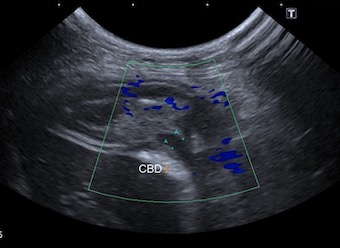

総胆管の拡張も認められ、十二指腸の開口部で閉塞を起こしている可能性が考えられました。